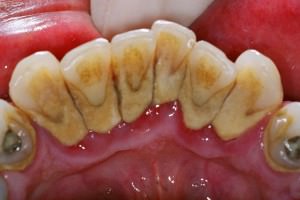

Даже невооруженным глазом зубы курильщика узнать достаточно легко, по специфическому налету на их поверхности и цвету зубной эмали. Но при ближайшем рассмотрении, если буквально заглянуть курильщику в рот, то можно увидеть так же следующие характерные проблемы:

- наличие темно-коричневого пигментированного налета в области шейки зуба;

- недостаточная увлажненность десны;

- болезненный бледно-розовый цвет слизистых оболочек;

- неприятный запах изо рта;

- и возможно даже воспаление тканей пародонта.

В первую очередь поражается область шейки зуба (переход зубной коронки в корень). Это место мало задействовано в процессе жевания и кроме этого плохо очищается с помощью зубной щетки.